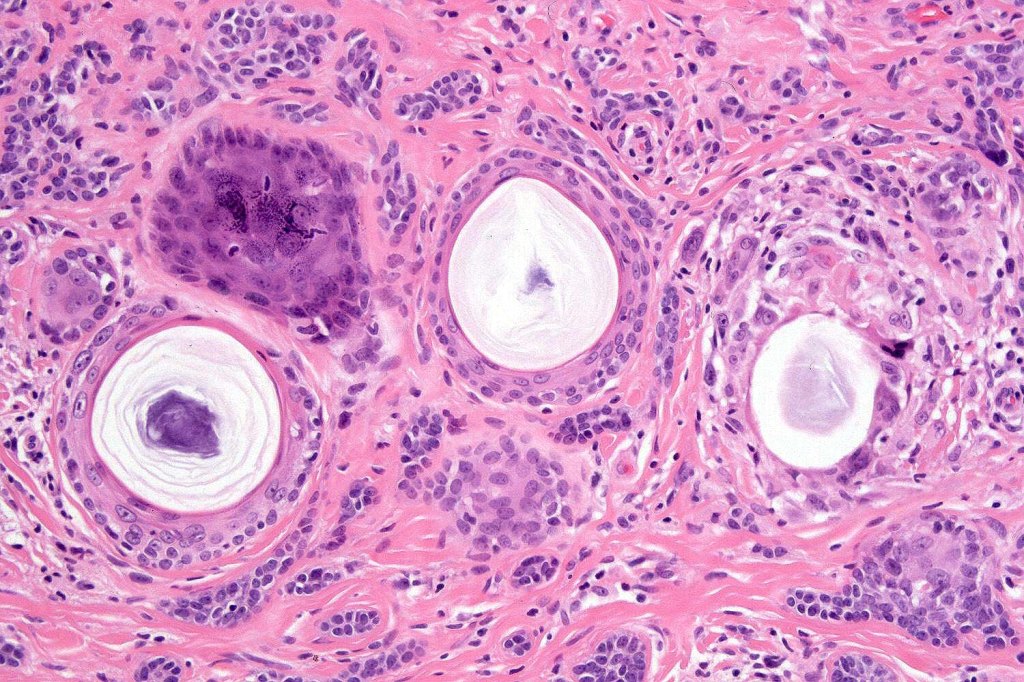

•Consists of narrow epithelial strands & keratocysts embedded in a dense stroma

•Calcification, foreign body giant cell reaction to keratin & bone are inconstant findings

•Epithelial stands may arise from follicular epithelium

•Can rarely see matricial differentiation

•Perineural infiltration is documented but is exceptional & makes differentiation from MAC difficult